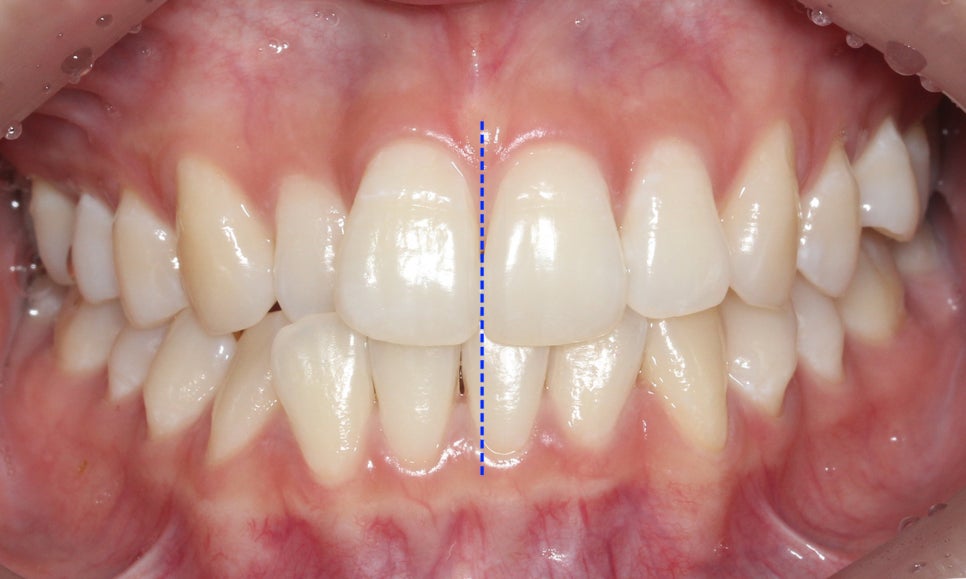

정면에서 본 치아의 전체적인 모습을 보면

상대적으로 구치부보다 전치부의 치열이

삐뚤어져 있는 상태로 12번(측절치)의

반대교합이 눈에 띄는 모습입니다.

치아 개방 시 상악과 하악의 정중선을 보면

대각선으로 삐뚤어져 있는 것을 확인할 수 있는데요,

안모의 중심이 틀어져 있기 때문에 치아 개방-교합 시

한쪽으로 힘이 가중될 가능성이 있습니다.